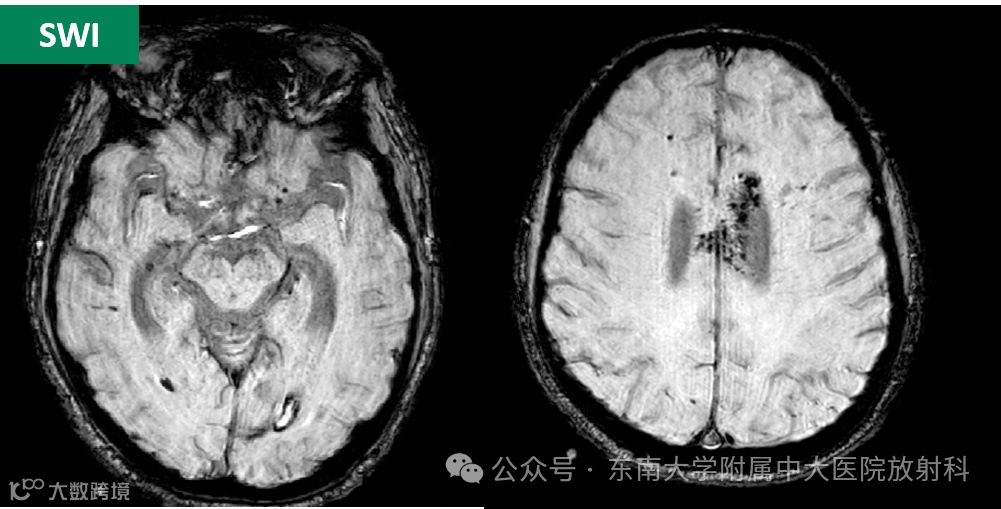

病史:患者1月余前自高处跌落,后立即出现昏迷,呼之不应。于当地医院就诊,头颅CT提示:双侧脑室积血伴脑内散在缺血腔梗灶,住院期间,予以高压氧、脱水、改善脑代谢、营养脑神经等对症治疗,病情缓解后转至南京紫金医院,予以康复治疗,病情稍改善,患者仍昏迷。现为求进一步诊治来我院就诊

影像学表现